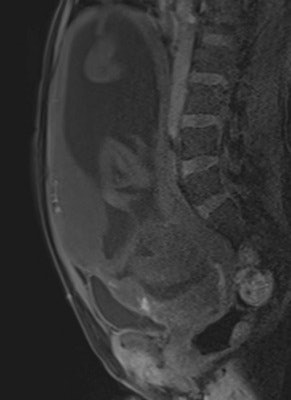

Their retrospective study included 25 pregnant women (mean age 35.16) -- 12 with histopathologically proven placental invasion and 13 without to act as a control -- who were investigated by prenatal MRI without IV contrast at three hospitals using three different 1.5-tesla MRI units (Magnetom Symphony, Siemens Healthcare; Intera, Philips Healthcare; Signa, GE Healthcare). The women underwent MR imaging between June 2007 and December 2009 after obstetrician referral for suspected placental invasion upon standard pregnancy ultrasound exams. The MRI protocols were similar and included T1-weighted volume interpolated gradient-echo MR sequences in the sagittal and axial plane, single-shot fast spin-echo T2-weighted MR sequences, and true fast imaging with steady-state precession in the axial, sagittal, and coronal planes.

Two senior radiologists with more than five years of practical experience in abdominal MRI and two junior radiologists with less than three years of abdominal MRI experience blindly and independently reviewed MR exams for six previously defined MR features described in the literature as useful for predicting placental invasion. The features included dark intraplacental bands on T2-weighted images, a focally interrupted myometrial border, heterogeneous intraplacental signal intensity, abnormal uterine bulging, "tenting" of the bladder, and infiltration of the adjacent pelvic organs.

In normal patients, the uterus presents as an inverted pear-shape organ. At MRI, the normal placenta appears as a soft-tissue structure, located along the uterine walls, with variable morphology and homogeneous, intermediate, signal intensity on T2-weighted images. In Alamo's study, T2-hypointense placental bands, a focally interrupted myometrial border, infiltration of the pelvic organs, and tenting of the bladder proved to be the best signs of predicting placental invasion.